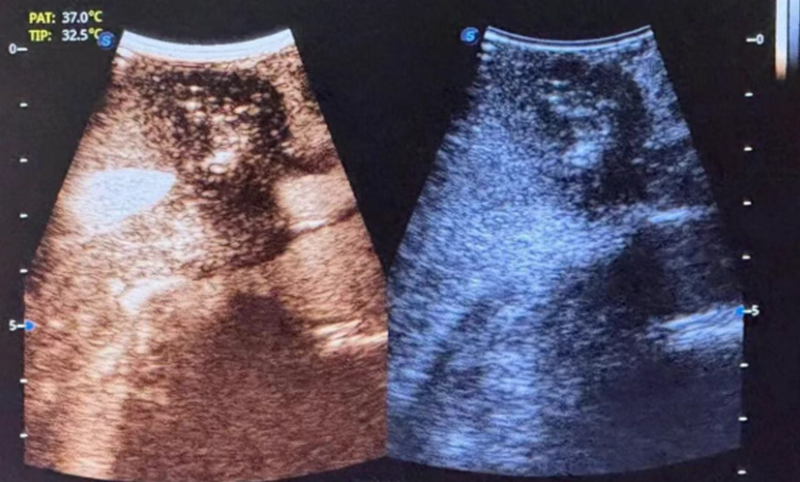

患者术前影像▲

患者女,63岁,以“全腹部不适2月”主诉入院,2月前饮食后出现全腹部不适,以右侧为主,腰背部疼痛,无恶心、呕吐,无反酸烧心等不适,外院行胸部及腹部CT示:双肺间质性改变,气管憩室可能,右侧第7肋骨陈旧性骨折可能,胰腺体尾部恶性占位,考虑胰腺癌可能,腹膜后稍大淋巴结,胆囊显示不清,胆总管扩张。术前检查发现病灶位于胰体尾部,大小为头足距3.5cm,左右距3cm,胸背距3cm。